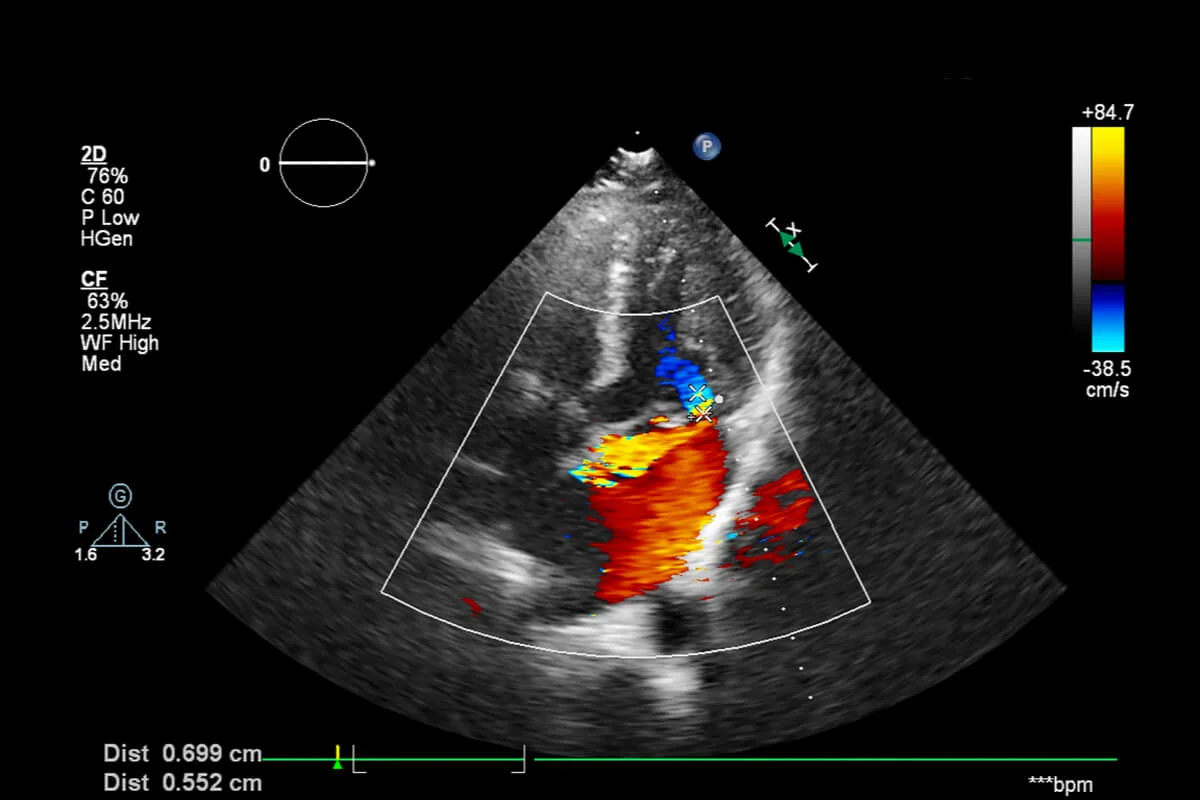

Doppler Ultrason, standart ultrasonografinin bir uzantısıdır ve yüksek frekanslı ses dalgalarını kullanarak vücuttaki kan damarlarında meydana gelen kan akışının yönünü ve hızını ölçmeye yarayan ileri düzey bir görüntüleme tekniğidir. Bu yöntem, özellikle gebelik takibinde plasenta ve bebeğin hayati organlarına giden kan akışını değerlendirmede ve bazı jinekolojik kitlelerin iyi veya kötü huylu olup olmadığını ayırt etmede kritik bilgiler sunar.

Doppler ultrason, standart ultrasona benzer şekilde, karın bölgesine jel sürülerek veya transvajinal prob kullanılarak uygulanır. Farkı, ses dalgalarının yansımasını renklendirerek veya grafik haline getirerek kan akış verilerini kaydetmesidir. İşlem tamamen ağrısız ve radyasyon içermez.